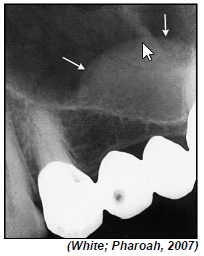

A análise radiográfica das bordas de lesões intraósseas e sua relação com estruturas anatômicas são importantes na definição de hipóteses de diagnóstico.

Defina uma hipótese de diagnóstico a partir da imagem radiográfica da lesão anterior.